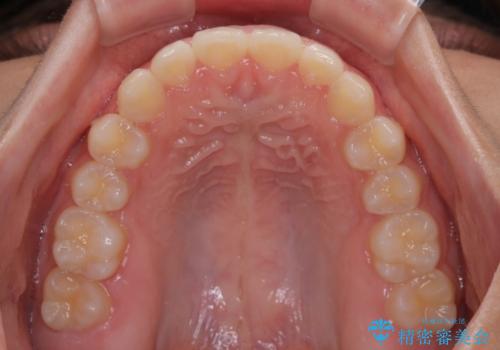

- 前歯の隙間を気にして来院された患者様です。

口元の突出感があり、小臼歯4本を抜歯して口元を引っ込める矯正治療も提案しましたが、本人は口元の突出感は気になっていないとのことで、インビザラインにて隙間やデコボコを改善することとしました。

軽度の歯列不正であったため、廉価版のインビザライン・モデレートパッケージにて治療を終えることができました。